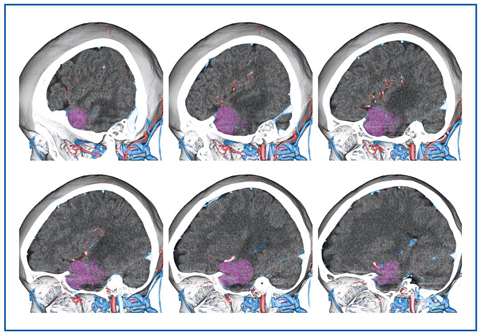

■脳腫瘍

以前は脳腫瘍においてCTAを行うことは少なかったが、最近は手術シミュレータ用のデータを得る目的で撮影することが多くなってきた。ziostation2では、腫瘍組織の血管、骨との位置関係を把握するための画像(図6)の提供や、bregma、nasion、inionなどの基準点や、正中などの基準線から腫瘍までの距離の算出を行い、術前情報として提供している。

図6 髄膜腫摘出術前

外側から3D断面を連続して観察することにより腫瘍、骨、血管の位置関係を見る。